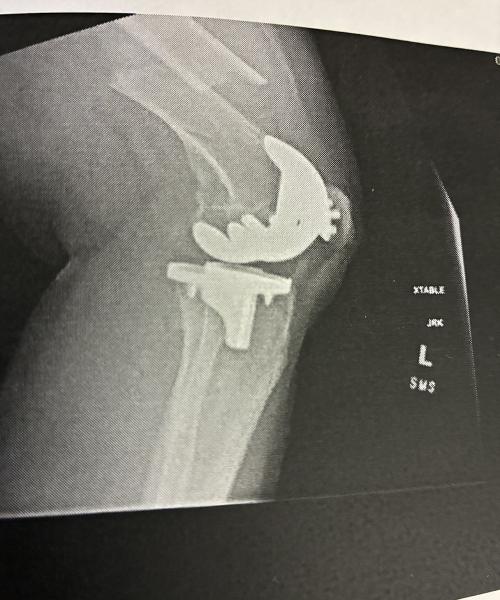

Painful and bad femur break

Fell and broke my femur. It was bad and very painful. I had surgery the following day. The doctor and whole staff were excellent and continue to be. It’s been 8 1/2 months and they have seen me through it all with great follow up and concern. They have set me up with wonderful in home physical therapy and now out-patient therapy. When I had any questions or concerns about my leg, they always called me right back and were able to take care of me and my needs. I can never repay them for what they’ve done for me and will always remember their kindness, thoroughness, and full care throughout this whole time. Thank you all.